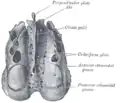

Visto de cima.

Visto de cima. Placa perpendicular ao etmoide.

Parede medial da órbita esquerda. Base do crânio. Superfície superior.

Base do crânio. Superfície superior. Parede medial da fossa nasal esquerda.